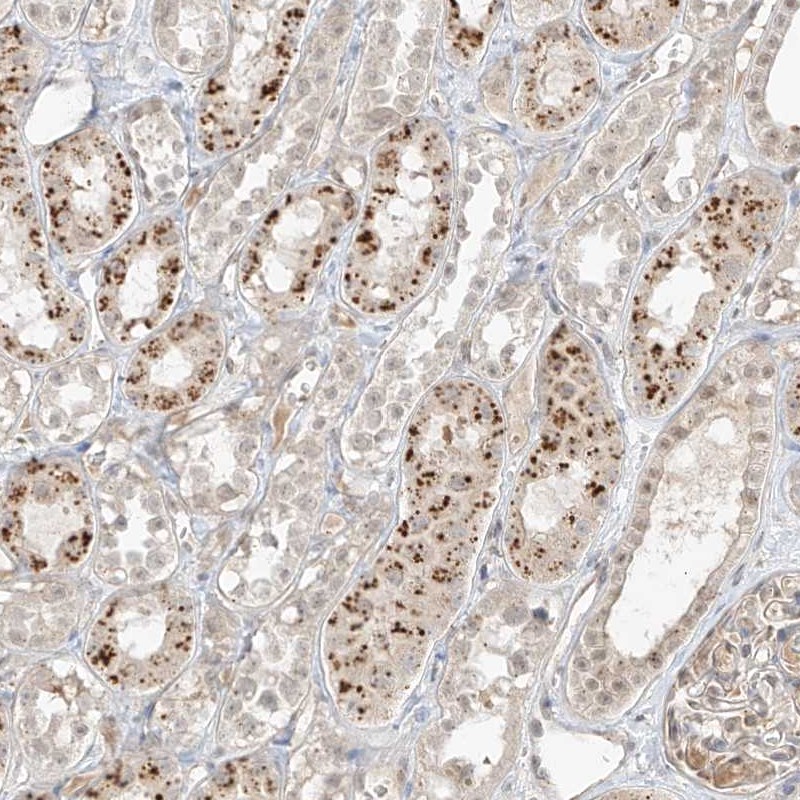

Immunohistochemical staining of human kidney shows strong granular positivity in tubular cells.